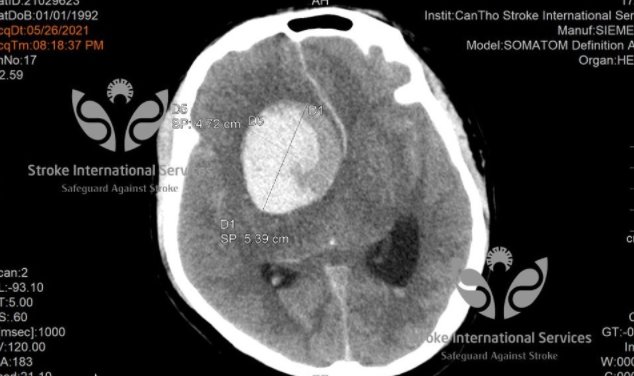

TS Trần Chí Cường – Giám đốc BV đa khoa quốc tế Cần Thơ chia sẻ về một trường hợp bệnh nhân nam 29 tuổi được đưa vào bệnh viện cấp cứu trong tình trạng đau đầu dữ dội, hôn mê sâu. Người nhà cho biết, trước đó, bệnh nhân đã bị đau đầu và đi khám uống thuốc nhưng không đỡ. Theo bác sĩ, bệnh nhân có một túi phình mạch máu não khổng lổ, kích thước lên tới 5cm (tương đương với kích thước của một quả chanh). Túi phình bị vỡ khiến bệnh nhân lâm vào nguy kịch.